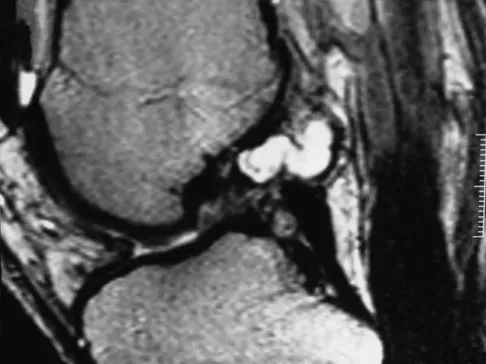

A 19-year-old girl has had pain and swelling in the right ankle for the past 4 months. She denies any history of trauma. Examination reveals a small soft-tissue mass over the anterior aspect of the ankle and slight pain with range of motion of the ankle joint. The examination is otherwise unremarkable. A radiograph and MRI scan are shown in Figures 45a and 45b, and biopsy specimens are shown in Figures 45c and 45d. What is the most likely diagnosis?

Explanation